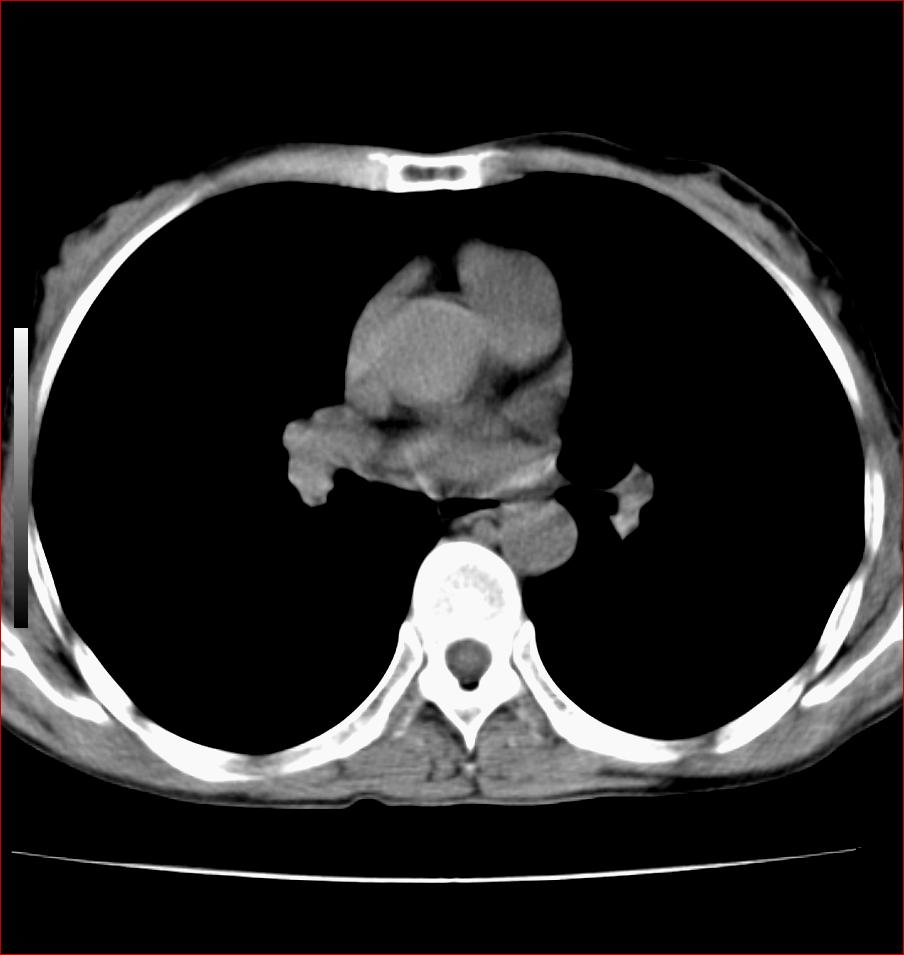

标题: CT17110:F56Y,纵隔囊肿;胸腺?淋巴?请各位老师看看 [打印本页]

女性患者 56 咽痛伴声嘶10+天入院。

纵隔囊肿,气管来源可能性大

纵隔囊肿,气管来源可能性大,建议强化。

纵隔前肠性囊性,支气管囊肿可能性大

支气管囊肿或淋巴管囊肿